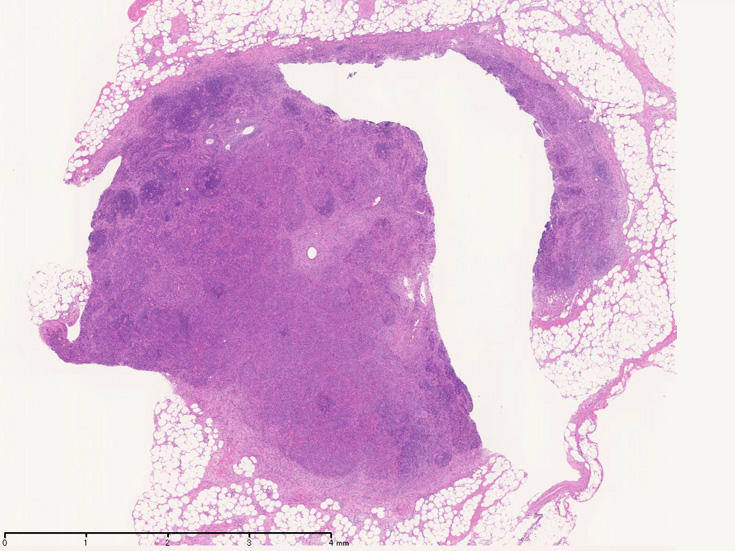

開腹リンパ節生検(腹膜脂肪組織内リンパ節, 割が入っている)

Virtual Slide---> 腹膜リンパ節 now available

腹膜脂肪組織内から生検されたリンパ節は基本構造を失っている。低倍率のHE所見では異型細胞が不鮮明な結節構造を形成して増殖している。一次リンパ濾胞を腫瘍細胞が置換しているように見える所見がある。